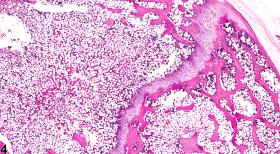

Decreased bone can result from either decreased bone formation or increased resorption of preexisting bone. The lesion is characterized by thin or absent bony trabeculae and/or thin cortices (Figure 1, Figure 2, Figure 3, and Figure 4). Microfractures may be observed. In lesions with active bone resorption, there are increased numbers of osteoclasts along a scalloped, irregular surface of trabecular bone, which represent osteoclastic effects on Howship''s lacunae (resorption bays). A diffuse decrease in bone may result from metabolic disturbances, whereas a focal decrease in bone may result from a pathologic process occurring focally within a bone, such as fibro-osseous lesion or osteomyelitis. Disuse (atrophy), as in the case of injured limbs or joints, may lead to a diffuse decrease within a particular bone.

Bone - Decreased bone in a female B6C3F1/N mouse from a chronic study. There is focal thinning of cortical bone and loss of metaphyseal trabeculae (arrowheads).